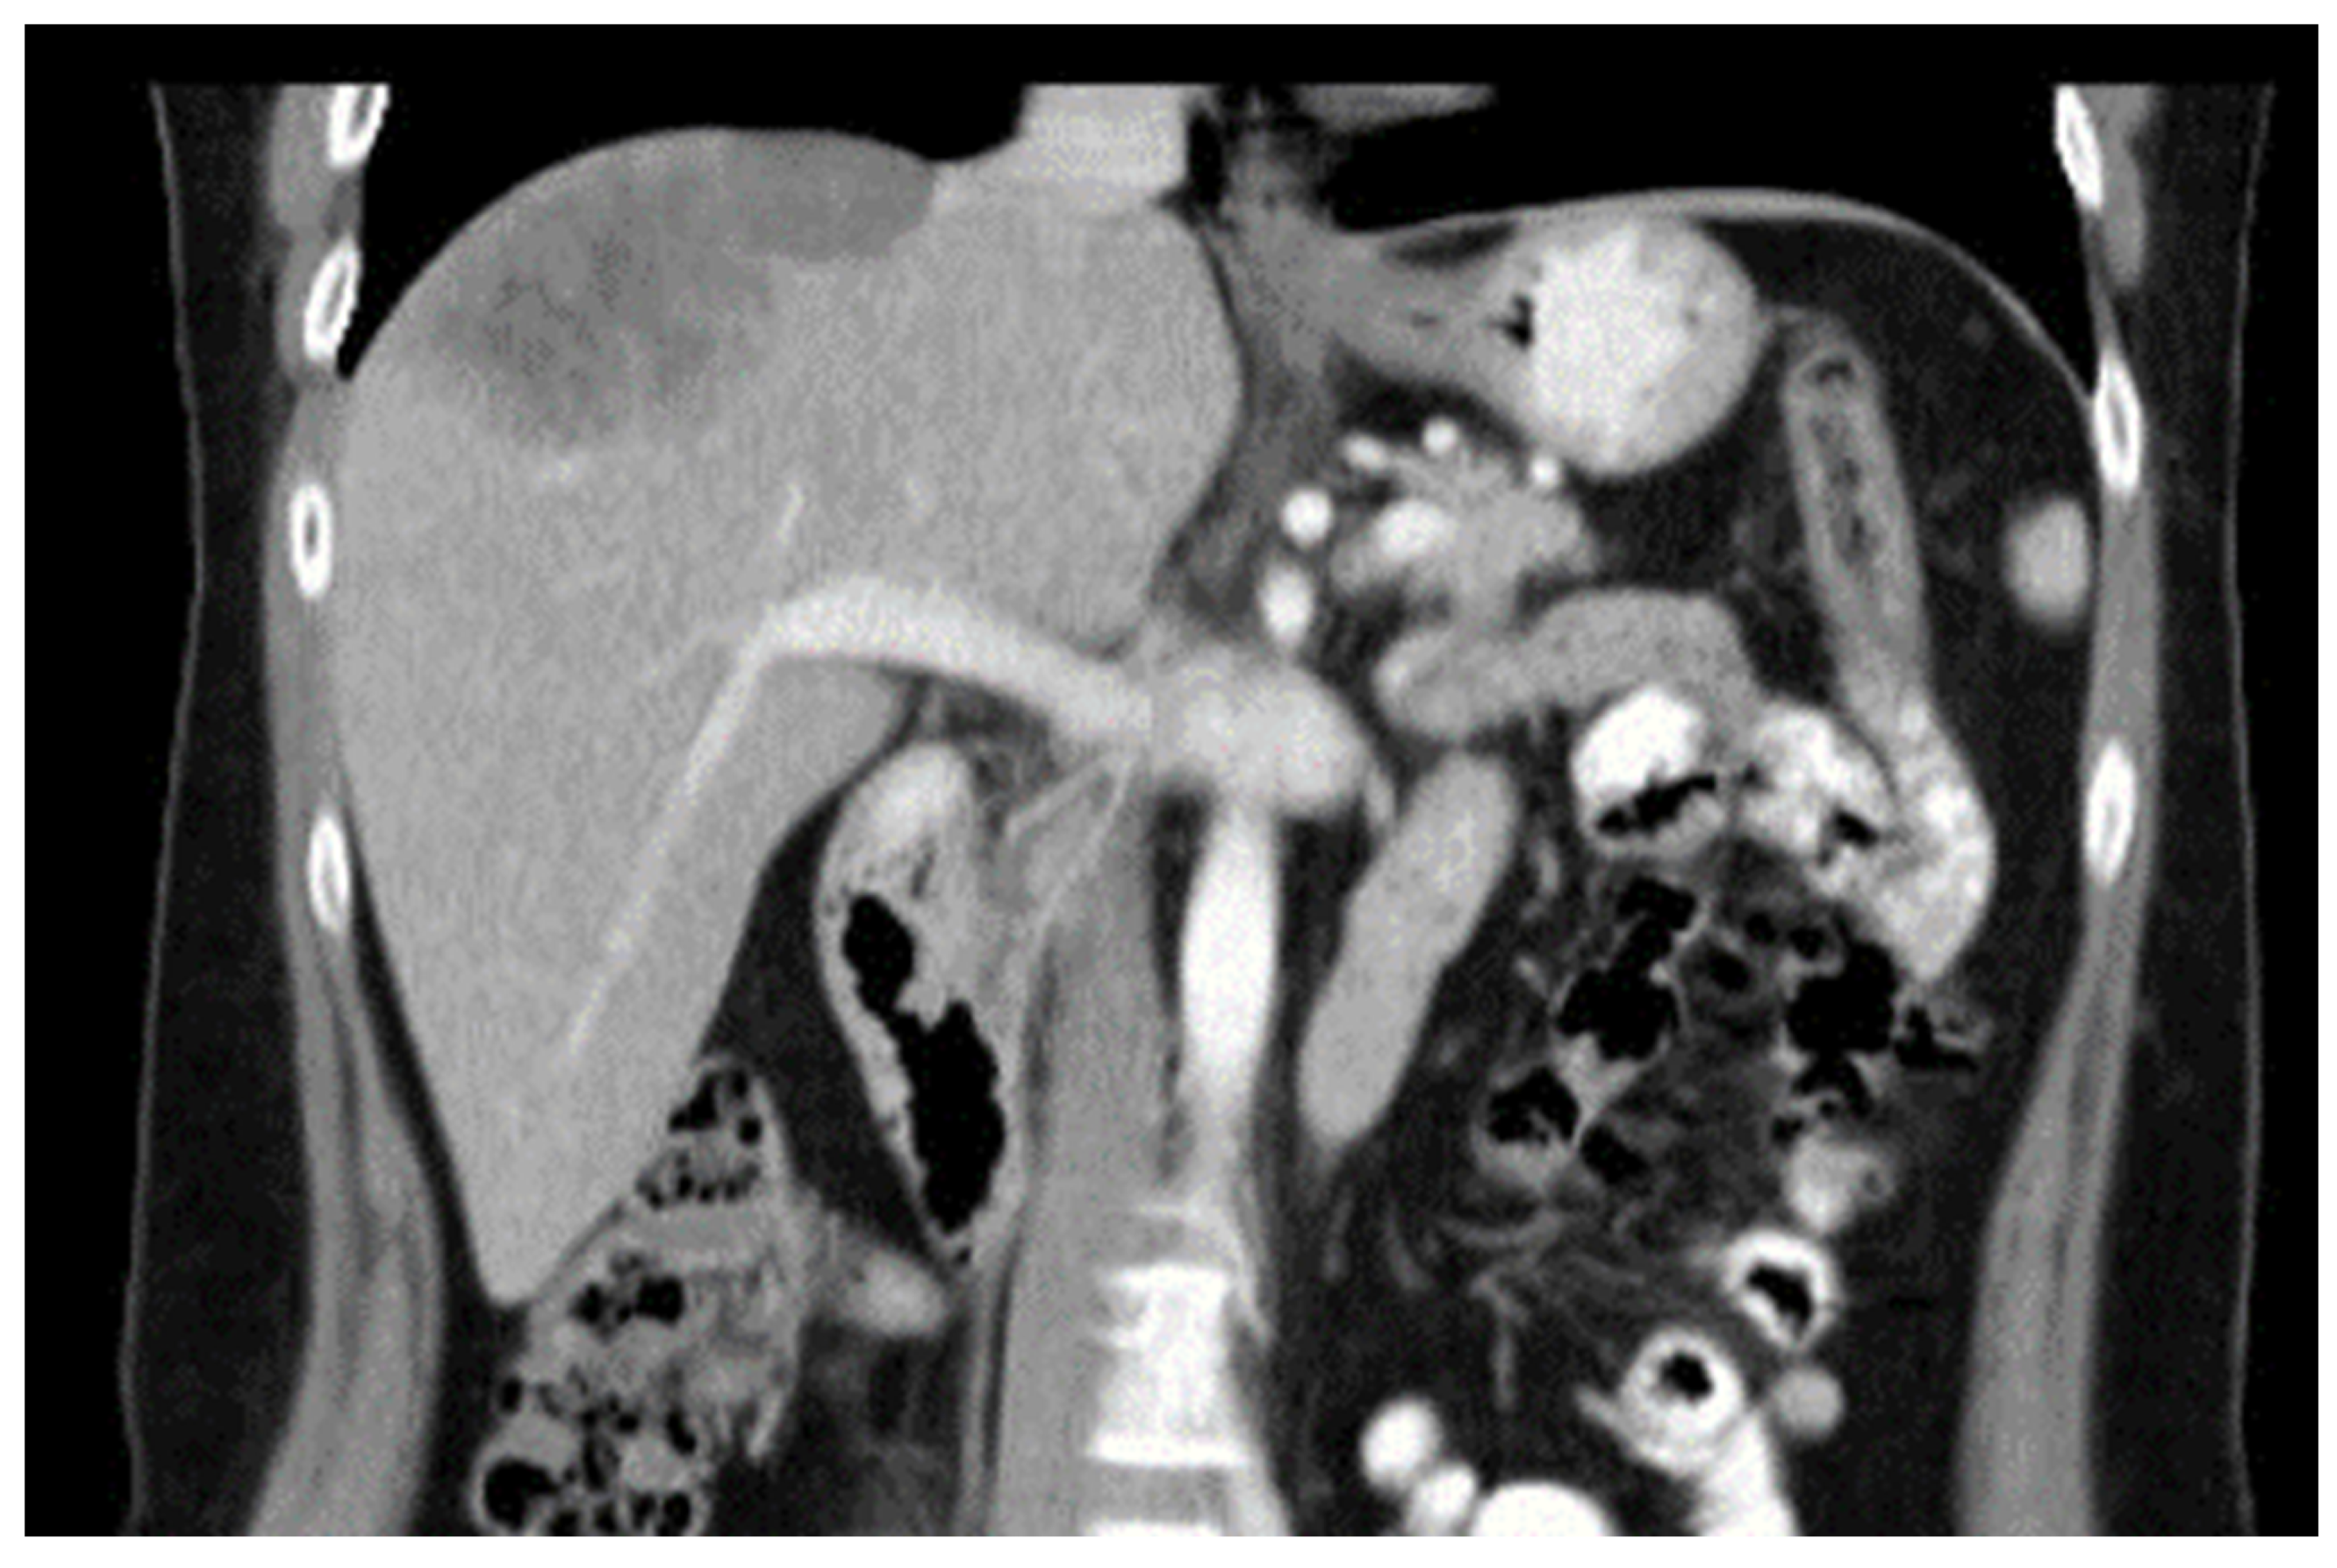

Diaphragmatic Liver Herniation after Radiofrequency Ablation of a Secondary Liver Tumor

Hoskovec, D.; Hořejš, J.; Krška, Z.; Argalácsová, S.; Klobušický, P. Diaphragmatic Liver Herniation after Radiofrequency Ablation of a Secondary Liver Tumor. Diagnostics 2024, 14, 26. https://doi.org/10.3390/diagnostics14010026